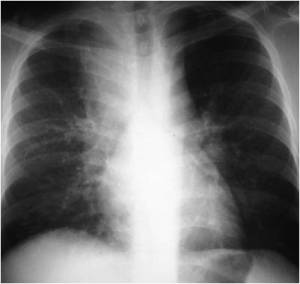

The following are examples of how Active TB may look on CXR:

Primary TB – LLL Infiltrate.

Mimics any pneumonia; occurs in debilitated pts, when Mtb first enters lung, and innate immune system unable to contain it.